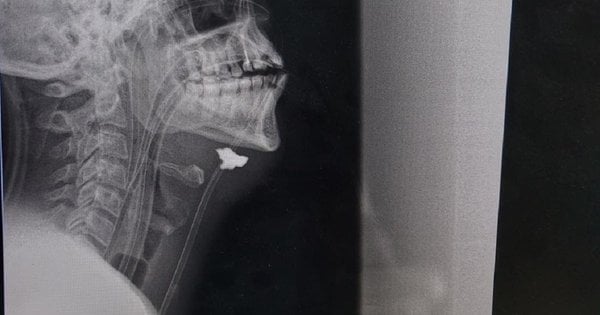

„Po vyšetření bylo u pacienta diagnostikováno střelné a střepinové slepé zranění. Fragment byl nalezen v projekci cévního svazku, hematomu a známkách poranění krční tepny vpravo. Jinými slovy, úlomek projektilu zasáhl rameno, prošel celým krkem, protrhl krční tepnu a zastavil se pod čelistí,“ řekl nám Taras Kobza, cévní chirurg, který dlouhodobě zachraňuje vojáky na východě země.

Jak vysvětlili cévní chirurgové ve Lvově, je velmi obtížné zachránit pacienty s poraněním krční tepny, mohou zemřít doslova za 5-10 minut od okamžiku poranění v důsledku velké ztráty krve nebo dostat mrtvici. Kapitán byl přijat do frontové nemocnice několik hodin poté, co byl zraněn. Podle chirurga ho zachránil fakt, že se v místě prasknutí krční tepny vytvořily krevní sraženiny (ochranná reakce těla), které uzavřely průsvit cévy a poněkud zpomalily krvácení. Ale ztratil hodně krve.